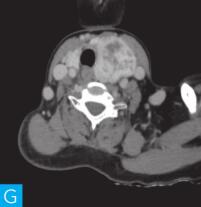

甲状腺CT检查:CT检查设备为256层iCT,病人采取仰卧位,扫描范围自外耳道平面至下颌角以下,常规扫描层厚为0.9mm、层间隔0.9mm,电压120kV,管电流280mA,矩阵512×512;经右肘静脉团注法增强扫描,碘海醇80ml,流速4ml/s,动脉期25秒扫描,静脉期60秒扫描。见图1。

图1 甲状腺CT

A、B.甲状腺CT横断面平扫;C~H.甲状腺CT横断面增强

答案A 解析:甲状腺左叶病变边界清楚,形态较规则,密度不均匀,部分为实性改变,部分为囊性灶,其内可见斑点状粗大钙化灶,气管及食管向右推移,左侧颈总动脉向左后推移,胸锁乳突肌向左前推移。根据表现病变不是单纯囊性病变。

答案C 解析:该病灶病史时间长,无发热及疼痛;病变位于一侧甲状腺,边界清楚;甲状腺血流及静态显像示:甲状腺左叶较大“凉”结节。因此不考虑恶性肿瘤及感染性病变。病变强化特点为结节状改变,呈现肿块样,故考虑肿瘤样病变。

CT平扫可见甲状腺左叶圆形以低密度为主病灶,大小为8.0cm×6.5cm,边界清晰,边缘尚光整,其内密度不均匀,低密度区CT值18HU,部分密度稍高,并可见斑点状粗大钙化影;CT增强后,甲状腺左叶病变呈不均匀渐进性强化,结节状改变,动脉期强化区CT值99HU,静脉期CT值85HU,且强化范围增大,提示该病变的血供较为丰富,应该考虑肿瘤样病变,结节性甲状腺肿可能性大。

本病例CT扫描发现起源于甲状腺较为容易,但要观察病变是囊性、实质性或囊实性及其供血,CT增强扫描十分必要,易于显示囊实性病变及其供血情况,其结节状改变更加显著,有助于判定病灶的血液供应情况。本病例基本征象为类圆形、边缘清晰、内粗大钙化、结节状强化之肿块。

该例病变位于甲状腺左叶,左叶不对称性增大,其内多发散在不规则强化结节影,斑点状粗大钙化,钙化周围可见星状伪影,提示钙化为长期慢性形成,而且钙化比较致密。肿块虽然很大,但与邻近气管、食管及血管等无明显侵犯或浸润征象。病变内部可见多发囊变区,增强检查实性部分呈明显均匀强化,包膜完整。双侧锁骨上区未见肿大淋巴结。提示病变为良性。病变多发,伴囊变、钙化,临床为中老年女性病人,颈前无痛性肿物。结节性甲状腺肿诊断明确。结节性甲状腺肿常常较大,术前影像学的评估包括:①病变的范围,累及胸骨下的范围决定手术治疗的方式,手术是否需要打开胸骨;②病变与气管的关系,是否具有气管软化,如果存在气管软化,要提醒临床医生手术过程中以及术后出现呼吸困难;③注意是否合并甲状腺癌,尤其是乳头状癌。要仔细寻找包膜是否完整,内部有无微小的乳头,以及邻近Ⅵ区或Ⅳ区是否伴有淋巴结转移。